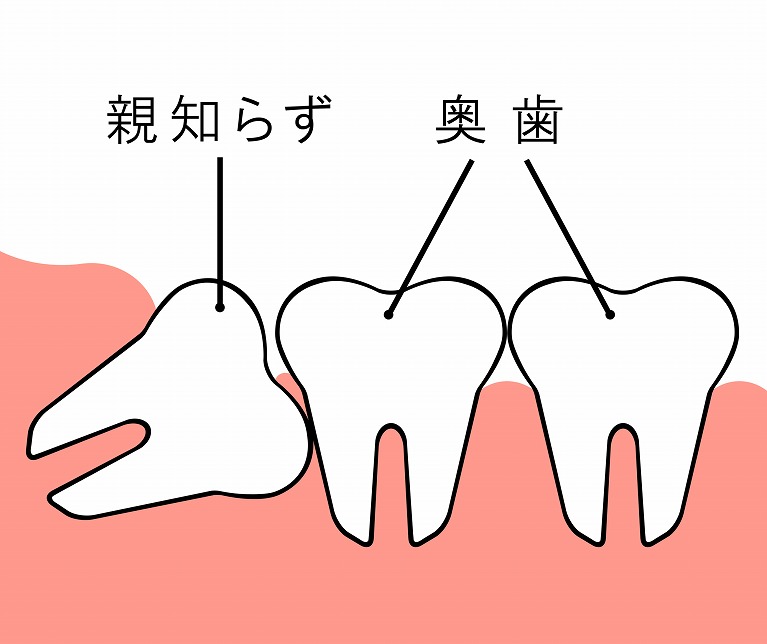

正常な智歯

まっすぐキレイに生えている状態。

まっすぐキレイに生えている状態。完全埋伏智歯